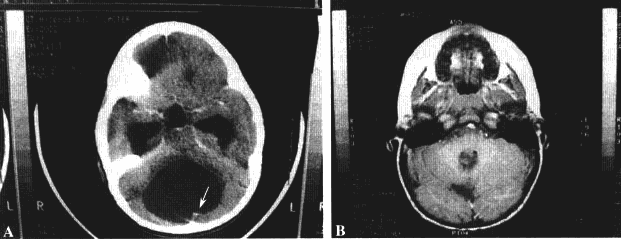

INC毛细胞性星形细胞瘤案例一则